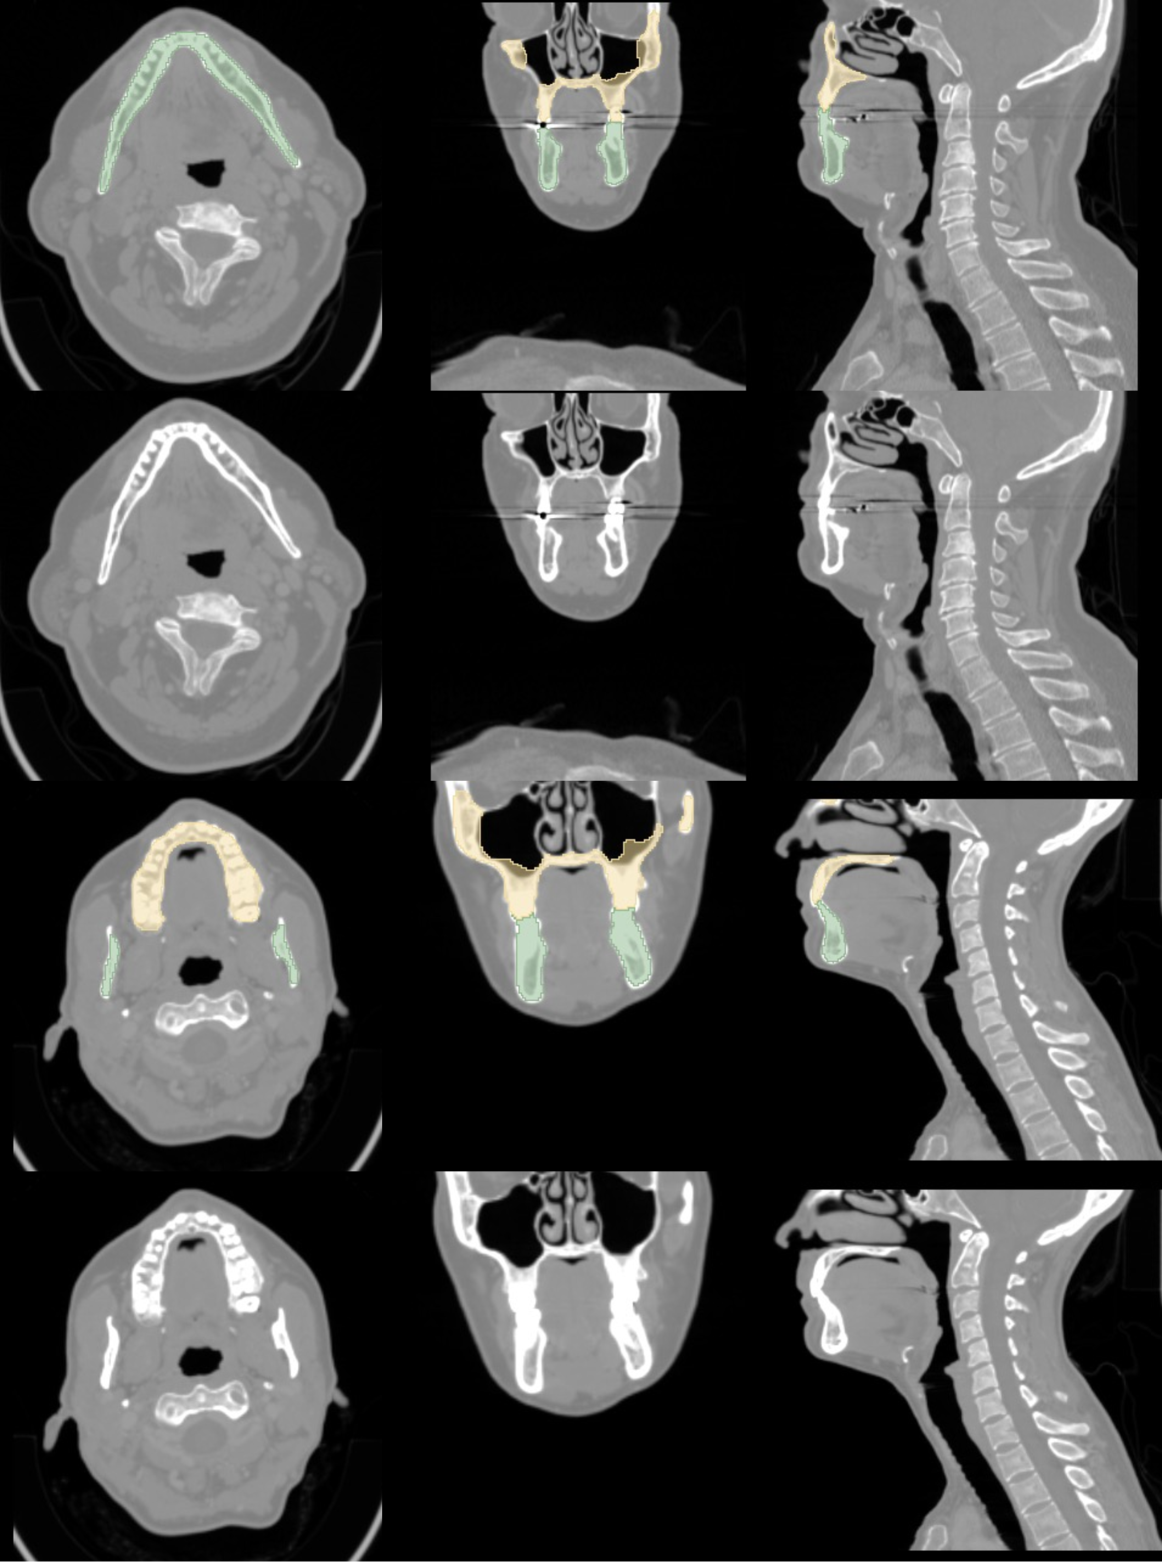

Refer to caption

Figure 2: Visual comparison between real and synthetic samples for both tumor and bone segmentation tasks. Top row: Real cases. Bottom row: Synthetic cases.

Using only synthetic data would improve privacy even further than conventional methods. To this end, we systematically evaluated the feasibility of using solely synthetic data and proposed several techniques to ensure its realism and utility. Accordingly, we focus on the crucial aspect of our research, highlighted in blue in Fig. 1, i.e. the study of the quality of synthetically generated CT and MRI scans using MAE, Multi-Scale Structural Similarity Index Measure (MS-SSIM), Radiomics and a VTT performed by 5 radiologists and their usefulness in segmentation of tumors and bone structures using Dice Similarity Coefficient (DSC). The two leading approaches for synthetic data generation cGANs and conditional DDPMs (cDDPMs) are used [27]. Our objective is to evaluate conditional approaches that facilitate the automatic generation of synthetic data and corresponding ground truth, thereby minimizing the need for specialist intervention and reducing their workload. We also employ two key and inherently time-consuming imaging modalities, MRI and CT, which are routinely used for diagnosis and treatment planning, as well as the segmentation task which is an essential yet labor-intensive task in the medical field, underscoring the need for high-quality results [28]. Fig. 2 illustrates a comparison between samples from the real dataset and synthetically generated with the respective segmentations for each task.

The portion of the dataset containing the segmentation labels was randomly split into 80% (n=778) for training (CTreal778𝐶superscriptsubscript𝑇𝑟𝑒𝑎𝑙778CT_{real}^{778}italic_C italic_T start_POSTSUBSCRIPT italic_r italic_e italic_a italic_l end_POSTSUBSCRIPT start_POSTSUPERSCRIPT 778 end_POSTSUPERSCRIPT) and 20% (n=195) for testing (Creal195superscriptsubscript𝐶𝑟𝑒𝑎𝑙195C_{real}^{195}italic_C start_POSTSUBSCRIPT italic_r italic_e italic_a italic_l end_POSTSUBSCRIPT start_POSTSUPERSCRIPT 195 end_POSTSUPERSCRIPT). The 285 without segmentations were then added to the training cases (778+285=CTreal1063778285𝐶superscriptsubscript𝑇𝑟𝑒𝑎𝑙1063778+285=CT_{real}^{1063}778 + 285 = italic_C italic_T start_POSTSUBSCRIPT italic_r italic_e italic_a italic_l end_POSTSUBSCRIPT start_POSTSUPERSCRIPT 1063 end_POSTSUPERSCRIPT ). The test cases are hidden for all training processes to ensure a fair assessment. Some examples of real cases can be seen in B and F.

The data was normalized by clipping between the quantiles 0.001 and 0.999 and linearly to the range [-1, 1]. The labels were split into three regions, the Enhancing Tumor (ET), the Tumor Core (TC) composed by the NeCRotic tumor core (NCR), and Peritumoral EDema (ED), and the whole tumor (WT) composed by the three segmentations (NCR+ED+ET). Approximately 80% of the dataset was randomly selected for training (MRIreal1000𝑀𝑅superscriptsubscript𝐼real1000MRI_{\text{real}}^{1000}italic_M italic_R italic_I start_POSTSUBSCRIPT real end_POSTSUBSCRIPT start_POSTSUPERSCRIPT 1000 end_POSTSUPERSCRIPT), and the remaining 20% reserved for testing (MRIreal251𝑀𝑅superscriptsubscript𝐼real251MRI_{\text{real}}^{251}italic_M italic_R italic_I start_POSTSUBSCRIPT real end_POSTSUBSCRIPT start_POSTSUPERSCRIPT 251 end_POSTSUPERSCRIPT). Some examples can be seen in C.